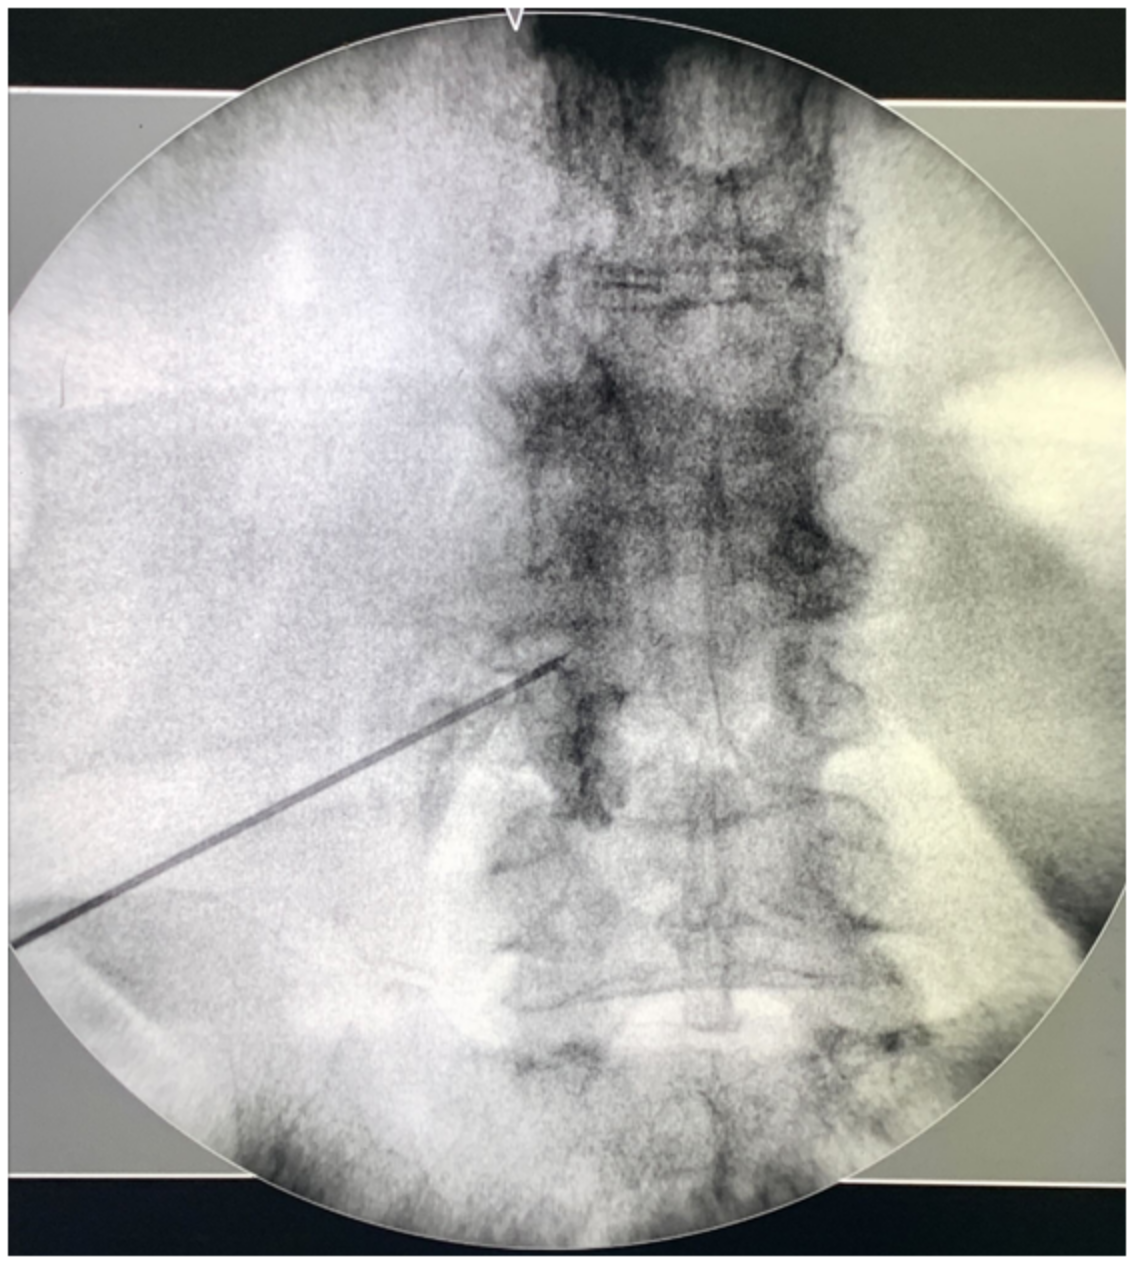

介入治療的常見選擇目前有脊椎硬膜外注射、微創內視鏡手術。硬膜外注射是用麻醉藥物、類固醇針對被壓迫的神經根進行注射。過程中會搭配X光讓醫師能定位神經的位置進行注射。